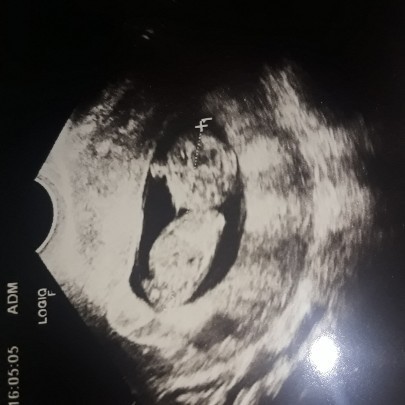

aku udh hamil 10w, tapi waktu kontrol ke bidan katanya belum teraba janinnya.. bunda2 dulu keraba dede nya waktu hamil berapa w?? ini masih normal kan bunn? bb ku juga turun 3kg ???

Dicoba usg bunda:)

aku 11w udh kelhatan bun

coba usg aja bun,

usg lbh jelas bun

3bulan baru teraba bun